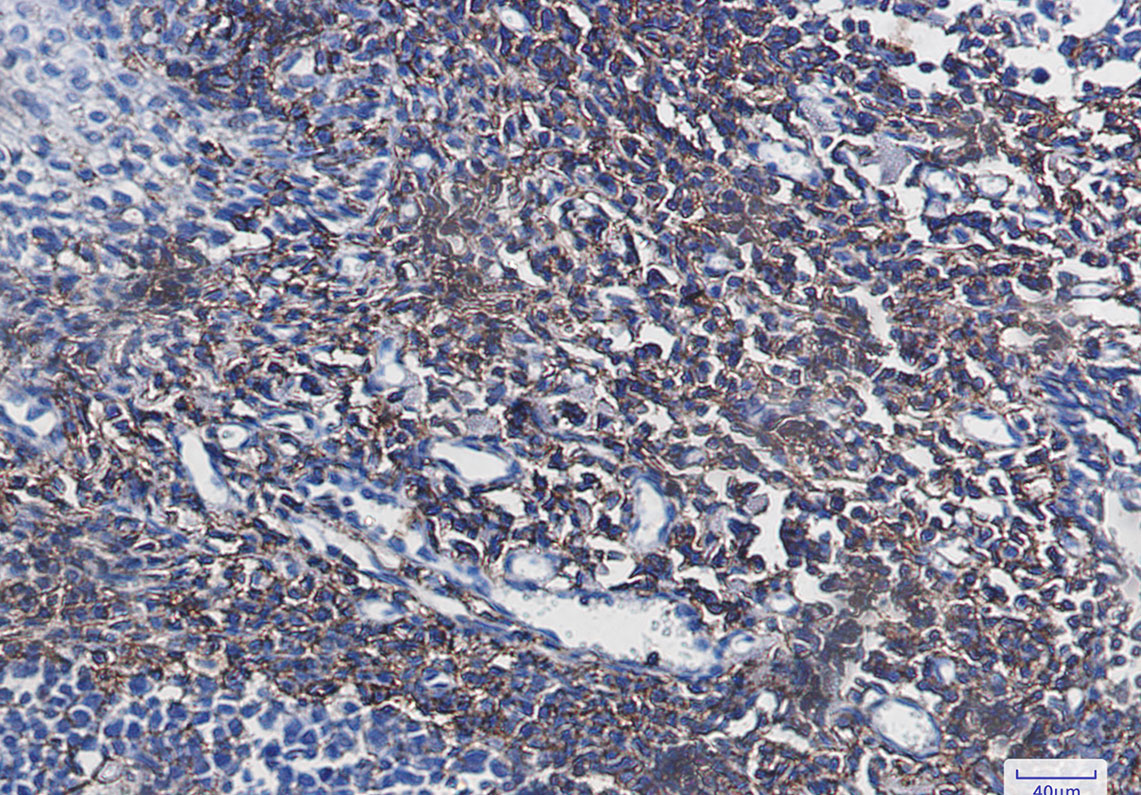

Product Image

- Immunohistochemistry analysis of paraffin-embedded Human tonsil using CD44 antibody. High-pressure and temperature Sodium Citrate pH 6.0 was used for antigen retrieval.